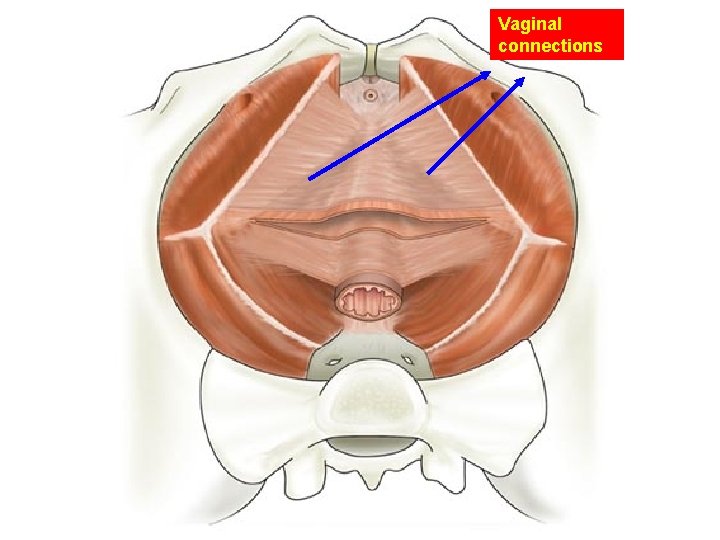

Vaginal connections